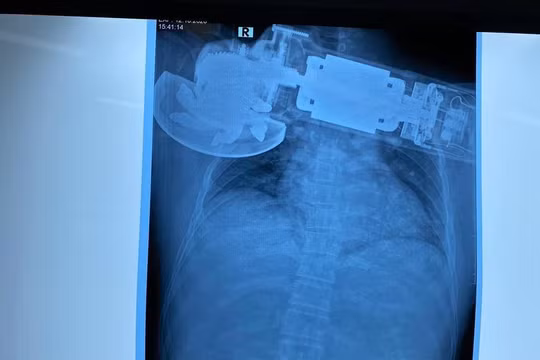

Viên đạn bắn xuyên cổ nam thanh niên 29 tuổi (Ảnh: BVCC)

Nam thanh niên 29 tuổi bị đạn bắn xuyên cổ vì dùng súng bắn chim tự chế

VietTimes – Các bác sĩ Bệnh viện Trung ương Quân đội 108 vừa cấp cứu nam thanh niên 29 tuổi bị đạn bắn xuyên cổ do dùng súng bắn chim tự chế.